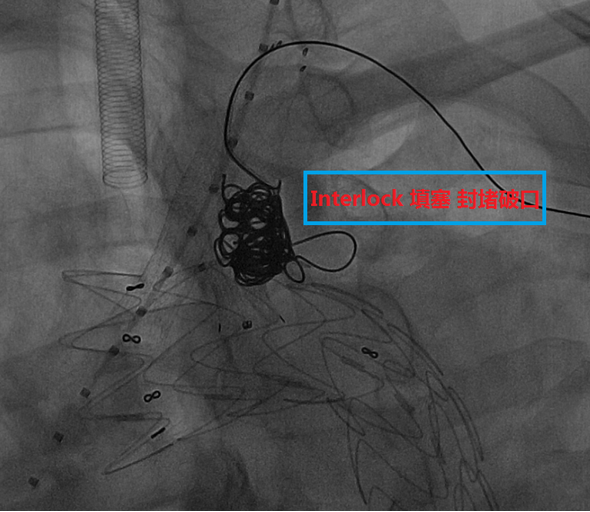

★ 病例1

73岁男性,主动脉夹层合并壁间血肿,心肺功能差,无法耐受开放手术。

手术关键步骤:

脑保护:经双侧锁骨下动脉置入8F长鞘至降主动脉,制造临时Ⅰ型内漏,再通过双供管连接颈动脉与肱动脉鞘管,建立转流通道,确保支架释放过程中脑部持续灌注。

支架定位与开窗:使用TAG CADS支架,释放至80%时造影调整位置,避免遮挡冠脉开口。

随后经左颈动脉穿刺,使用NPAS肝穿针原位开窗,逐级扩张后植入Viabahn支架。

右颈总动脉:相同操作,植入VBX支架,重建无名动脉系统。

远端覆盖:股动脉入路植入cTAG支架,与近端支架重叠,确保降主动脉以远血供。

锁骨下动脉二期重建。